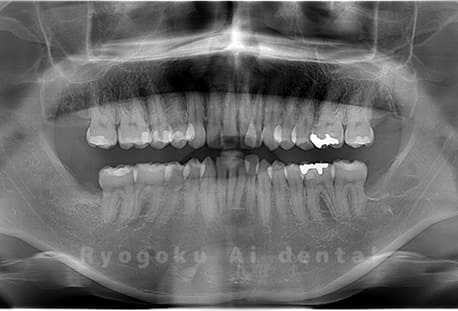

Case05

- 原因

- 下顎の親知らず2本

- 治療内容

- 下顎の親知らず2本を抜歯したケースです。

<リスク・副作用>

手術後は痛み、腫れ、痺れなどの副作用が生じる場合があります。